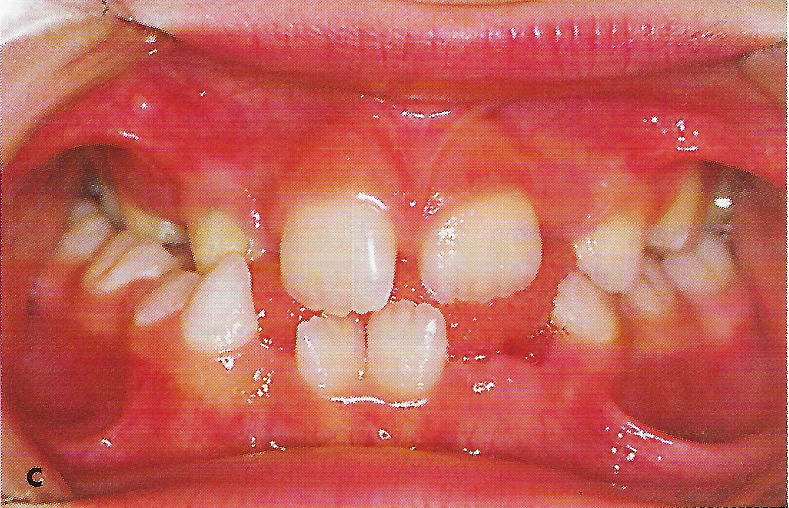

Abb. 1 a bis h Extra- und intraorale Ansicht der Patientin vor Behandlungsbeginn: Kopfbiß beziehungsweise umgekehrter Schneidezahnüberbiß und beidseitiger Kreuzbiß als Folge einer maxillären Hypoplasie sowie hälftenungleicher Mesialbiß infolge mandibulärer Verschiebung nach rechts.

• Ankylose Abb.1c

• Ankylose Abb.1d

Diese Patientin war zu Behandlungsbeginn 7 Jahre alt. Sie hatte einen hälftenungleichen Mesialbiß infolge mandibulärer Verschiebung mit Kopfbiß beziehungsweise umgekehrter inzisaler Stufe, rechtsseitigem vollem Kreuzbiß und linksseitigem doppeltem Höckerbiß, maxillärer Kompression sowie Platzmangel in beiden Kiefern (Abb. 1 a bis h). Die kephalometrische Analyse ergab eine progene Kieferlagebeziehung, bedingt durch eine unterentwickelte Maxilla bei vertikalem Gesichtsschädelaufbau.